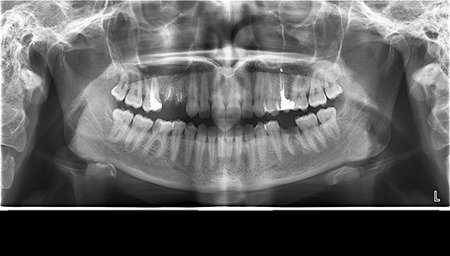

- Цифрова панорамна рентгенографія (ортопантомограма) – дає цілісне зображення всієї щелепно-лицевої системи.

Цифрова панорама Полтава: широкий погляд на здоров’я порожнини рота

Що ви уявляєте, коли лікар говорить про ортопантомограму? Насправді, це знімок усієї зубощелепної системи, який охоплює обидві щелепи, гайморові пазухи та скронево-нижньощелепні суглоби. Таке оглядове фото дозволяє стоматологу отримати загальне уявлення про стан зубів, кісткових структур та навколишніх тканин.

Ортопантомограма Полтава є незамінною при первинній діагностиці, коли потрібно оцінити загальний стан ротової порожнини. Її призначають у наступних випадках:

- для виявлення прихованих каріозних уражень;

- для оцінки стану пародонту (ясен і кістки);

- перед ортодонтичним лікуванням;

- перед видаленням зубів мудрості;

- для моніторингу росту та прорізування зубів у дітей.

Цифрова панорама Полтава успішно використовується для первинної діагностики в момент першого звернення до лікаря, бо дозволяє виявити всі патологічні процеси в зубах, кістці, навколощелепних тканинах. Завдяки їй лікар не припуститься помилок під час планування й виконання складних ортопедичних робіт.

Діагностика зубів Полтава із застосуванням ортопантомограми має ряд переваг:

- швидке та безболісне обстеження (триває всього кілька хвилин);

- мінімальна доза опромінення – робить процедуру безпечною навіть для дітей;

- загальний огляд усієї порожнини рота на одному знімку – максимальна інформативність для стоматолога;

- можливість зберігання знімків у цифровому форматі для подальшого порівняння та динаміки лікування.